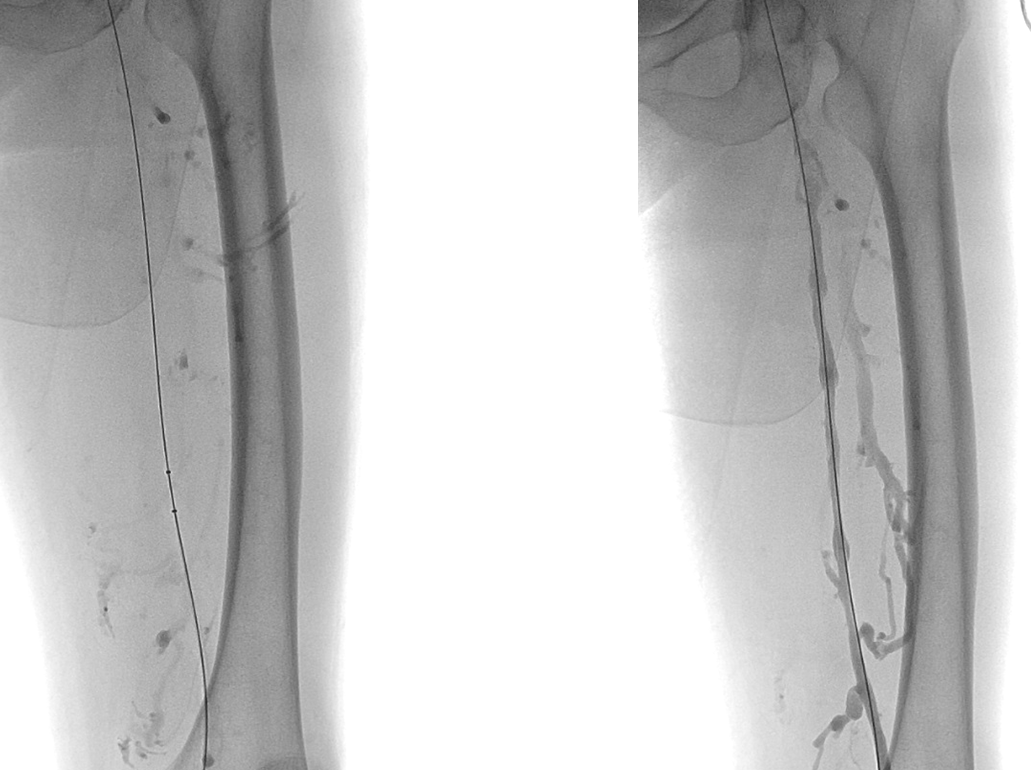

Simon导管翻山后导丝进入股深静脉,造影明确股深静脉血栓范围

股深静脉吸栓后通畅,于左髂静脉置入14*80mm支架,复查造影血流均通畅

3月超声随访:左股总、股浅、股深静脉均通畅